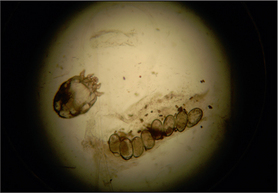

In this case, mites, faecal pellets and eggs were demonstrated on skin scrapings (Fig. 4.4).

Figure 4.4 Sarcoptes mite, several eggs and faecal pellets.